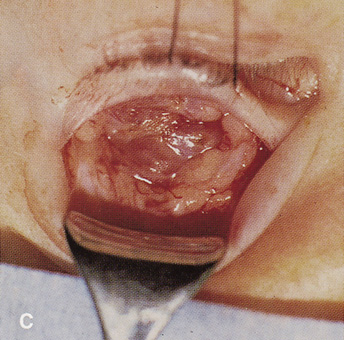

Lesions in the subperiosteal space that involve the orbital floor and roof of the maxillary sinus can be approached through an intraoral incision in the buccal sulcus above the upper canine incisors (Fig. 19). Dissection is carried through mucosa and soft tissue to the periosteum over the face of the maxilla. Dissection is carried superiorly in the subperiosteal plane to just below the inferior orbital rim. Care must be taken to identify the infraorbital nerve as it exits the foramen just below the rim. Osteotomies then are made in the face of the maxilla, and the underlying maxillary sinus is exposed. The sinus mucosa is excised and the roof of the sinus exposed in this fashion. Removal of the sinus roof (the orbital floor) allows exposure of the inferior periorbita. Care must be taken to avoid damage to the infraorbital nerve that runs within the bone of the floor. The inferior rectus muscle is encountered immediately above the periorbita, and it must be protected and retracted during deeper orbital dissection.

Fig. 19. Transantral inferior orbitotomy. The orbital floor (A) (roof of maxillary sinus) is exposed by an incision in the buccal sulcus and removal of the anterior face of the maxillary bone. The infraorbital nerve (B) traverses the floor of the orbit and exits on the face of the maxilla from the infraorbital foramen (C).

Indications

This approach often is used for orbital decompression in Graves' ophthalmopathy and cases of primary sinus pathology with secondary orbital involvement. It can be combined with a transconjunctival inferior orbitotomy approach to provide elevation and protection of orbital contents before removal of the orbital floor from below. It can be used to approach inferior peripheral lesions near the apex where an anterior-inferior orbital approach may not allow sufficiently deep access. However, better exposure may be afforded by a lateral orbitotomy in those cases.